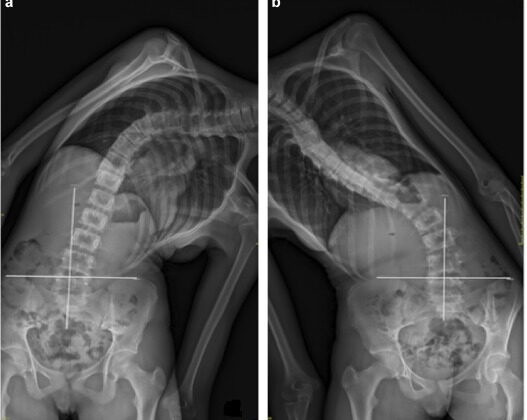

يتم قياس المرونة عادةً من خلال الأشعة الجانبية أو أثناء الانحناء الجانبي (Bending X-ray)، حيث يُطلب من المريض الانحناء إلى الجهة المعاكسة للانحناء، ويُقاس مقدار التصحيح الناتج.